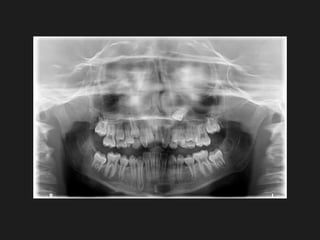

SUPERNUMERARY TEETH

Cleidocranial Dysplasia

Cleidocranial Dysplasia (CCD) is a rare congenital disorder of bone with an autosomal

dominant hereditary mode of inheritance. with complete penetrance, but variable expressivity.

This condition is characterized by clavicular aplasia or deficient formation of the clavicles,

delayed and imperfect ossification of the cranium, moderately short stature, and a variety of

other skeletal abnormalities. The principal oral manifestations are a delayed exfoliation of

primary teeth, delayed or multiple impactions of the permanent dentition, and multiple impacted

supernumerary teeth ( mechanical block to succedaneous theeth).